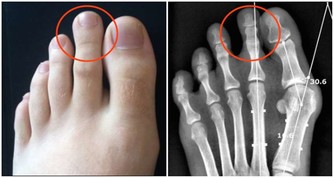

若有自體免疫疾病,如類風濕性關節炎、系統性紅斑狼瘡等,則須配合同時治療;